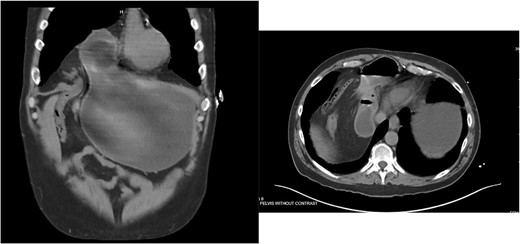

A 55-year-old male underwent lung cancer screening with a chest CT scan (Fig. 1) and was incidentally found to have an anterior diaphragmatic hernia just inferior to the sternum.

Approximately ten years prior, he had undergone coronary artery bypass surgery (CABG) with a xiphoidectomy. His symptoms at the time of the CT were right upper quadrant pain and epigastric fullness. He was referred for outpatient surgical evaluation. Shortly after the initial surgical assessment, he presented to the emergency department with gastric outlet obstruction. An abdominal CT was performed, showing a right-sided type 4 anterior diaphragmatic hernia with herniation of the antrum and pylorus causing the obstruction (Fig. 2). A loop of the transverse colon was also herniated into the thorax but without colonic obstruction.

Right-sided type 4 anterior diaphragmatic hernia with antrum and pylorus herniation.